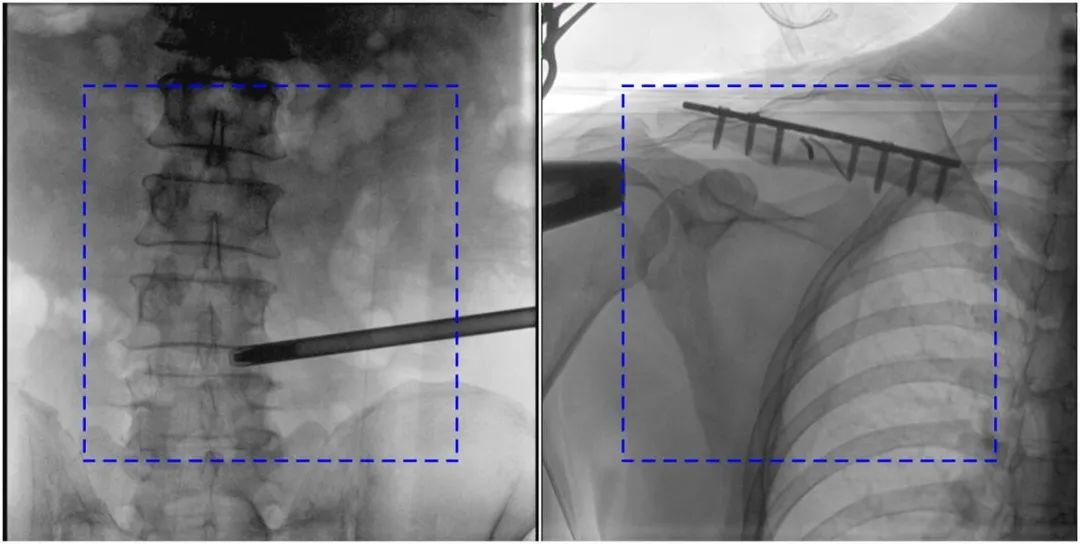

与传统的21CM×21CM成像尺寸相比,糖心vlog 大平板一体式C形臂具有30CM×30CM更大成像尺寸,能够一次成像5.5节椎体,呈现更全面的影像信息,即便是手术经验不丰富的年轻医生也能通过图像迅速判断椎体节段、定位手术部位,避免因为视野不足而造成的多次定位、反复曝光,提高效率的同时避免过量摄入辐射。

大平板一体式C形臂图像与传统图像对比(蓝色虚线内为传统21CM×21CM平板的成像区域)